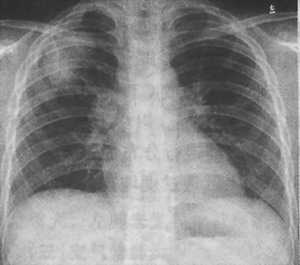

同时,结核杆菌还会沿着淋巴管通向靠近肺门的淋巴结,导致淋巴结肿大,这又叫原发性肺结核。临床上主要表现为咳嗽、周身不适、倦怠、午后低热、盗汗、体重减轻等症状。如果上述症状持续时间较长而没有特殊原因者,可能为肺结核早期症状,其胸片特异表现为“哑铃征”。

原发性肺结核“哑铃”状胸片,箭头所指为结核初发病灶(图片来源:life.yxlady.com)